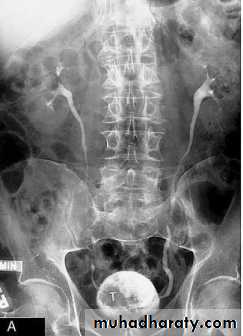

Horseshoe kidneys

The kidneys are also orientated with the lower pole closest to the midline, which is the reverse of normalThe anomaly is readily detected on conventional urography. In 90% of crossed ectopy, there is at least partial fusion of the kidneys